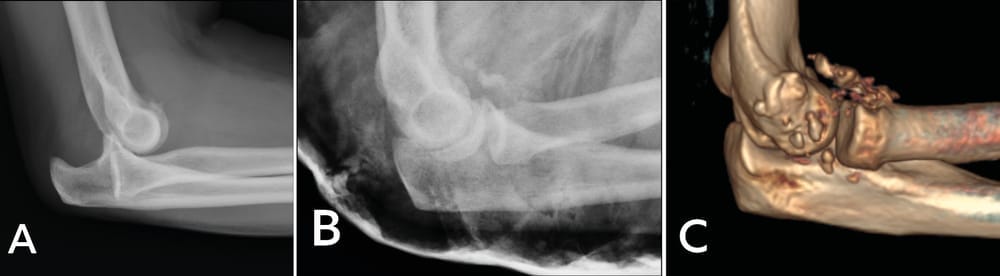

Case study 1: A 49-year-old right-handed male electrician fell from a stepladder, which led to bilateral elbow fracture dislocation (Mason 4). An emergency closed reduction was performed. Subluxation of the left elbow persisted, with damage to the ulnar nerve. After CT investigation (Figure 3), ORIF appeared to be possible, a more viable option since a prosthetic radial head would not be available for at least 5 days.

ORIF of the radial head seems to be accessible from the left side. After exposure, reconstruction proves not to be possible. A capitellum graft is harvested and fracture repair is achieved through a Medartis plate (Figure 4).